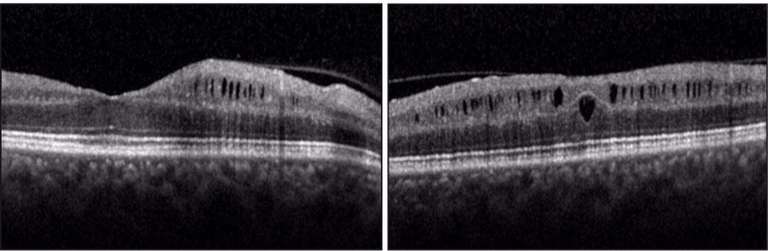

Un tableau atypique de drusen papillaires : un train peut en cacher un autre - cahiers-ophtalmologie

Un tableau atypique de drusen papillaires : un train peut en cacher un autre - cahiers-ophtalmologie from www.cahiers-ophtalmologie.fr